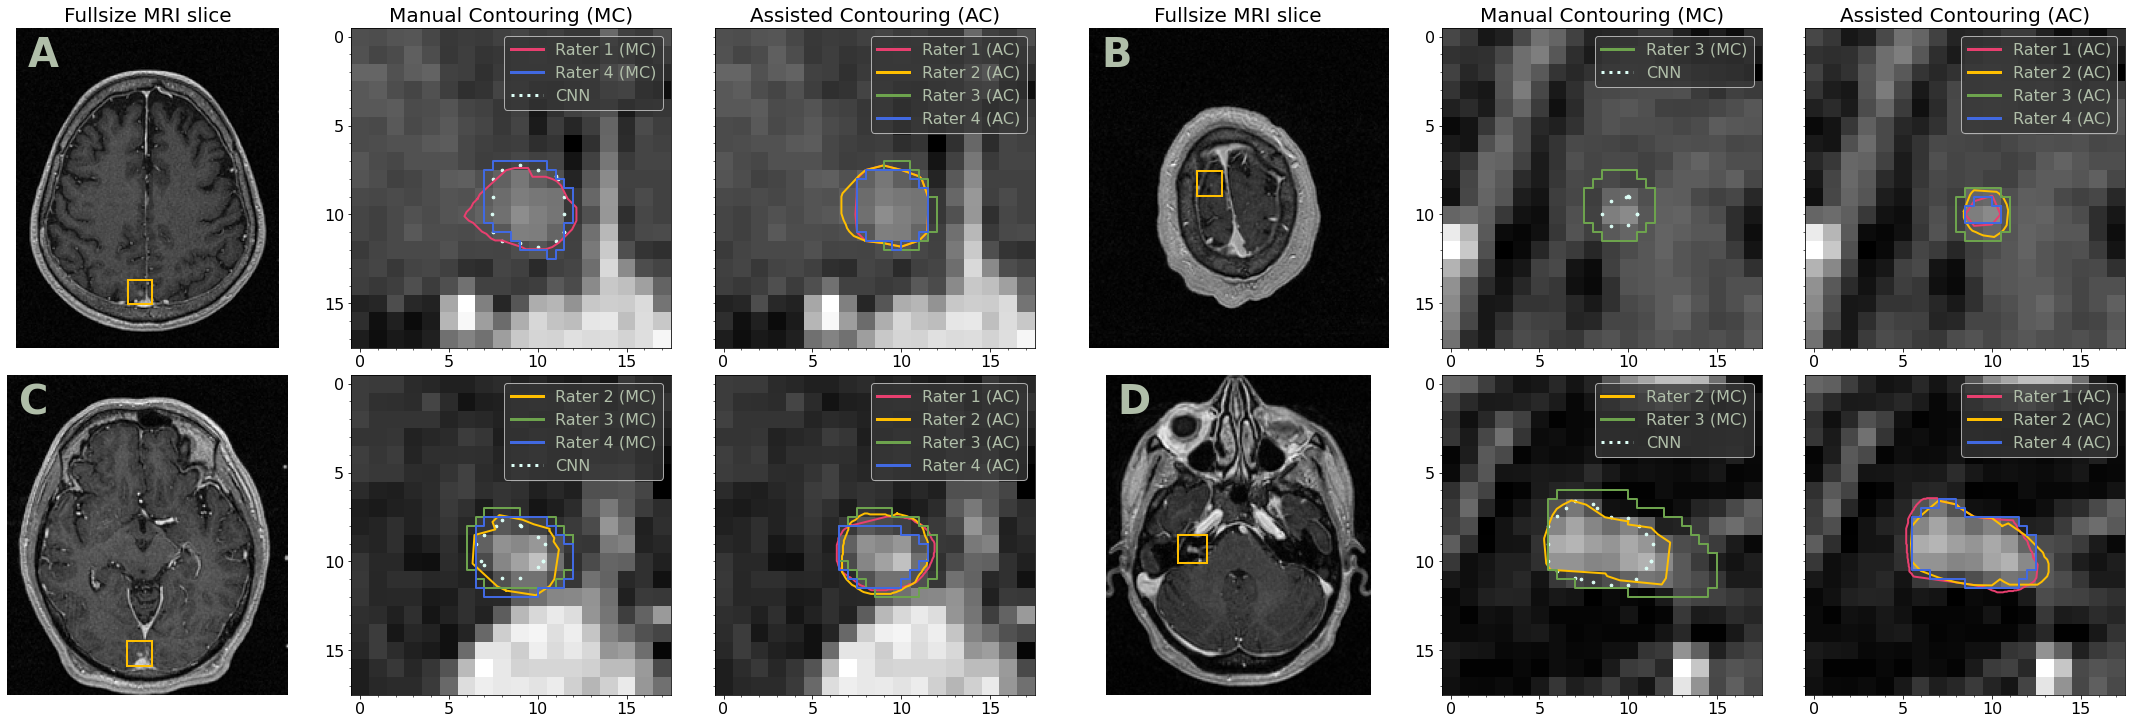

Therefore, both CNN and raters tend to miss or mistakenly delineate small lesions. The examples of such False Positives are given in Fig. 3. The reduction of False Negatives (or the increase of Recall) when switching from MC to AC is shown in Fig. 4.

Refer to caption

Figure 3: Examples of False Positive delineations made by raters or CNN. The falsely detected objects are mostly small tumors that might be considered as vessels or have a non-typical localization. In every pair, we show a 2D slice (left) and the zoomed region with the contours (right). In-plane MRI resolution is 0.9375×0.93750.93750.93750.9375\times 0.9375 mm. Only delineated contours are plotted.